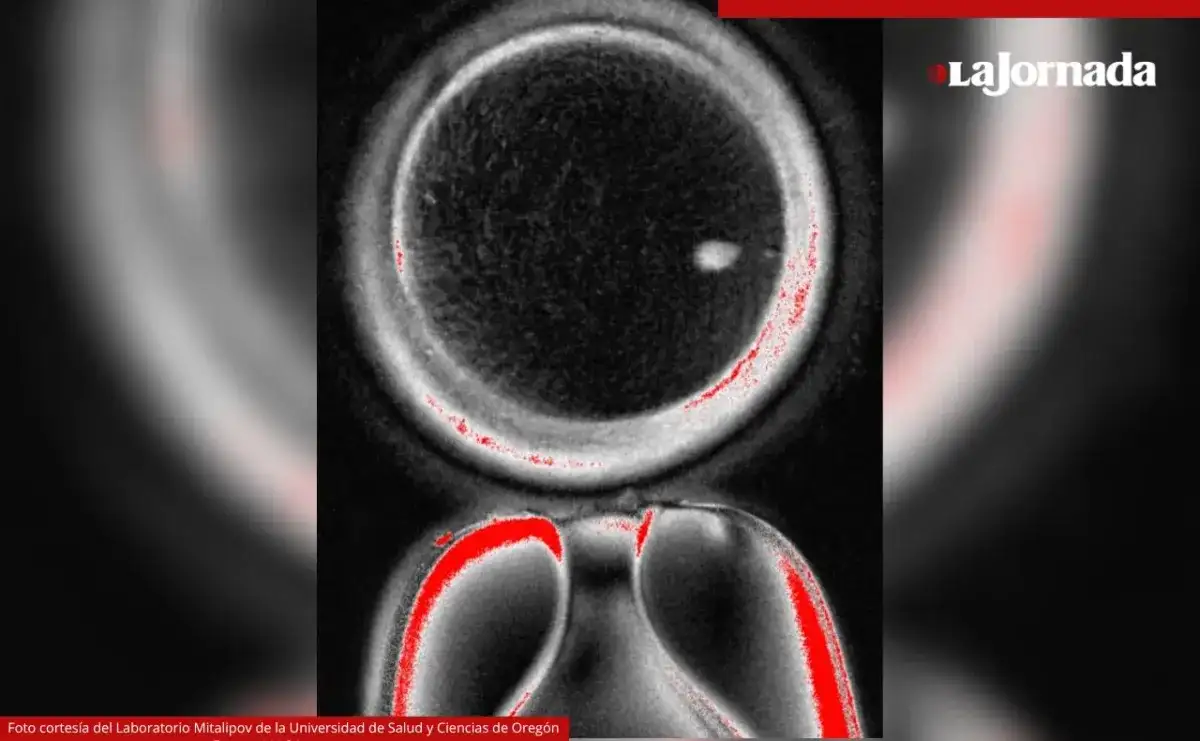

El Laboratorio Mitalipov de la Universidad de Salud y Ciencias de Oregon proporcionó esta toma de microscopio de un óvulo humano que contiene un núcleo de una célula de la piel. Foto

El Laboratorio Mitalipov de la Universidad de Salud y Ciencias de Oregon proporcionó esta toma de microscopio de un óvulo humano que contiene un núcleo de una célula de la piel. Foto Ap

Primero, los científicos extrajeron el núcleo de células de la piel y lo transfirieron a un óvulo donado al que previamente se le había retirado su núcleo. Esta técnica, llamada transferencia nuclear de células somáticas, fue utilizada para clonar a la oveja Dolly en 1996.

La investigación podría ser una respuesta a la infertilidad, que afecta a una de cada seis personas en el mundo. Foto cortesía del Laboratorio Mitalipov de la Universidad de Salud y Ciencias de Oregón